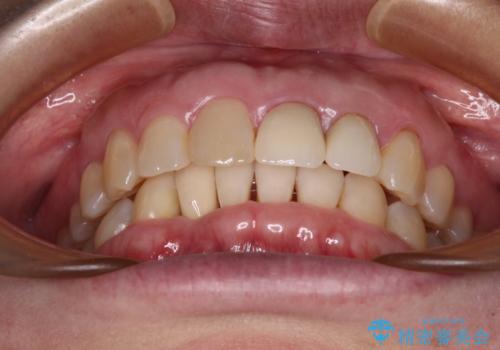

- 下顎前歯が抜けそうとのことで来院された患者様です。

初診の状態ではすぐにでも抜けそうな状態で、インプラントによる補綴治療を行うこととしました。

インプラント治療に際し、前歯の叢生に対する矯正治療を提案したところ、興味を持たれたので、インビザライン・ライトによる矯正治療を行うこととしました。

抜歯後にスペースができると恥ずかしいため、抜歯した歯を接着剤で固定した上で矯正治療を行い、その後インプラントやオールセラミッククラウンの装着を行うこととしました。